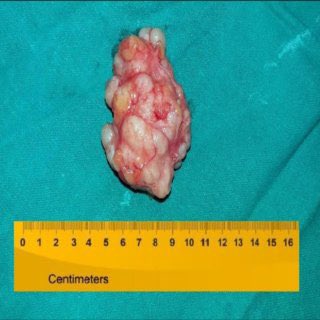

5️⃣وقد تكون بسيطةً باحجام تتراوح بين 1-3 سم أو عملاقة

يزيد عن 5 سم،لا تتسبب بحدوث إفرازات من حلمة الثدي أو تورم وأحمرار. تبدأ بالتكون في الفصيصات المنتجة للحليب فتكبر الأنسجة وقنوات الحليب المحيطة لتشكل في النهاية كتلة متماسكة وليّنة ويصبح قوامها وخشونتها أشبه بملمس حبال الربط

-أورام ليفية: تنشأ في الأنسجة الضامة حجمهابين 1-3 سم أوأكبر من ٥ سم وظهورها لا يجعل المرأة المصابة بها أكثر عرضة من غيرها للإصابة بسرطان الثدي.هي شائعة الحدوث بين كثير من النساء والفتيات خصوصا بين 15 - 35 و